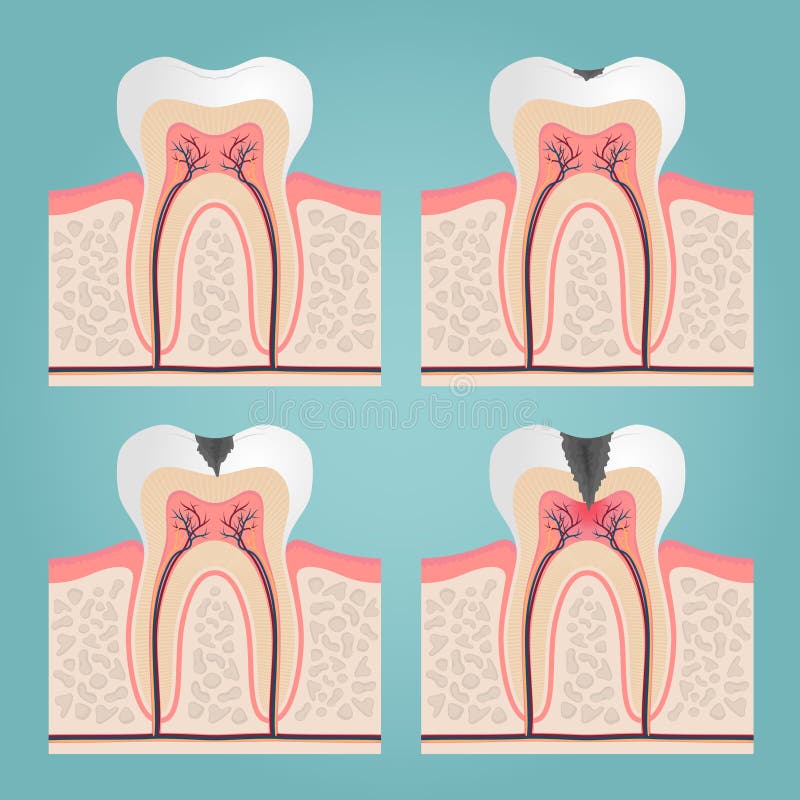

Tanden strukturerar Medicinskt diagram av strukturen av det inre tvärsnittet av tanden